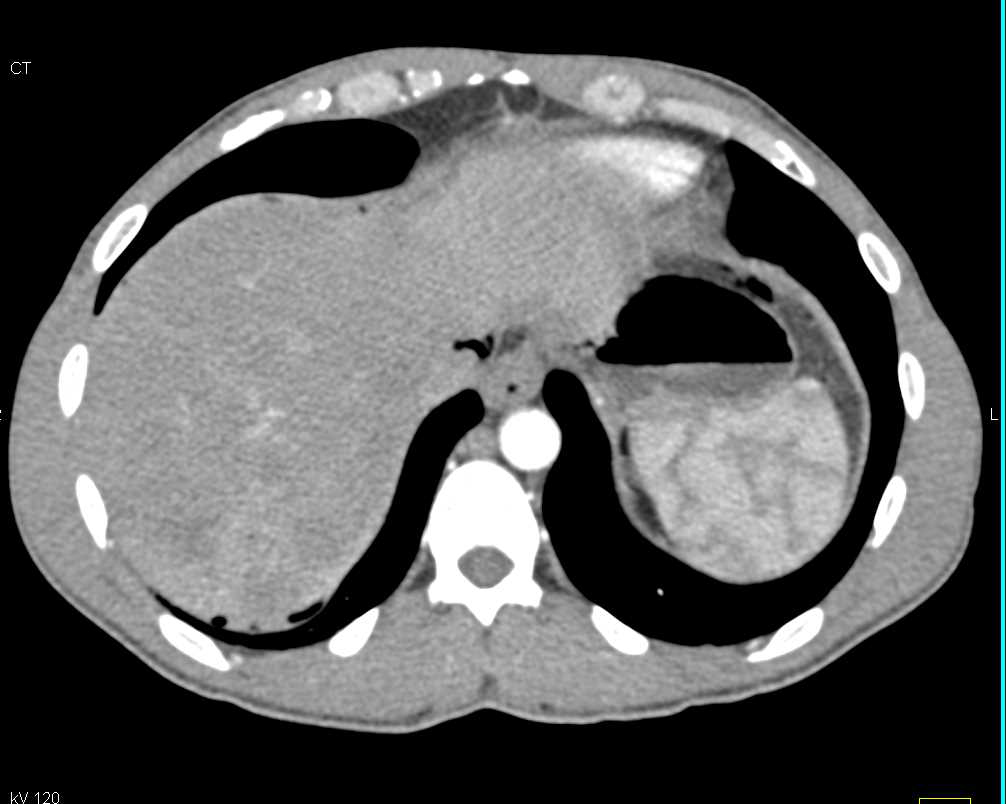

Carcinoid Tumor Root of Mesentery with Misty Mesentery and Vessel Encasement